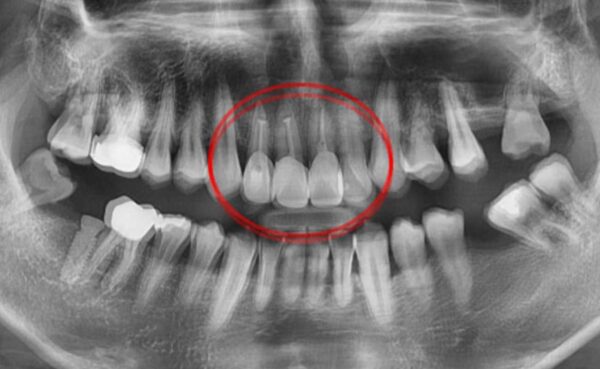

이미지 위에 가운데 동그라미를 클릭한 상태에서 왼쪽 또는 오른쪽으로 드래그해보세요! 드래그할 때마다 환자의 전후 변화를 확인하실 수 있습니다.

#자연치아보존 치근단절제술 환자 사례 : 드림연합치과 치근단절제술 사례 전후